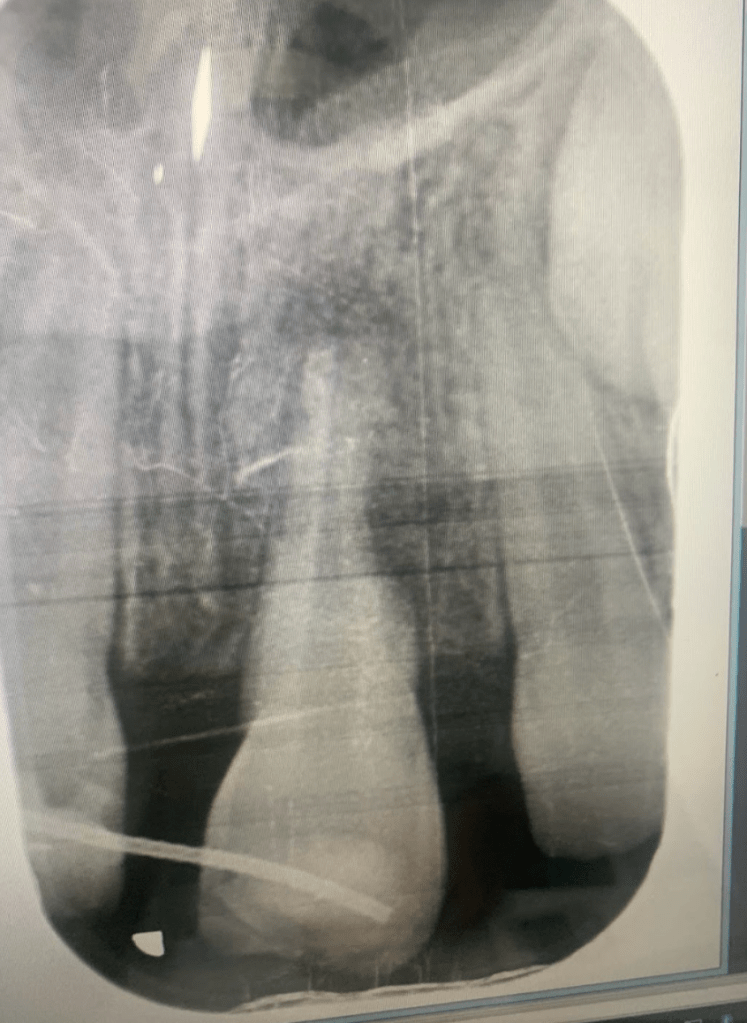

Avulsión incisivo central